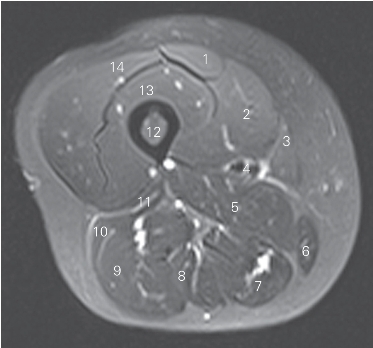

图5-12 经股骨中份的横断层MR T2WI FS

1 股直肌 rectus femoris 2 股内侧肌 vastus medialis

3 缝匠肌 sartorius 4 股动静脉 femoral artery and vein

5 大收肌 adductor magnus 6 股薄肌 gracilis

7 半膜肌 semimembranosus 8 半腱肌 semitendinosus

9 股二头肌长头 long head of biceps femoris

10 股二头肌短头 short head of biceps femoris

11 外侧肌间隔 lateral intermuscular septum

12 股骨 femur 13 股中间肌 vastus intermedius

14 股外侧肌 vastus lateralis